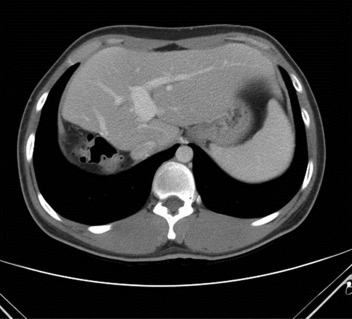

Computed tomography of the donor 5 months after surgery.

Figure 7.

The operation time of graft harvest was 415 minutes. Estimated blood loss was 150 mL, with no need to transfusion for the donor. The donor was allowed to resume oral intake on postoperative Day (POD) 1 and full meals on POD 4. Subcutaneous hematoma was found in the Pfannenstiel incision and improved after wound care. He was discharged home in a stable condition on POD6. At follow-up of 12 months, there was no complication especially in terms of the biliary tree (Fig. 7). The recipient experienced one episode of pneumonia after transplantation but remained complication free later on.